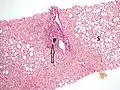

Pathology

Micrograph showing cirrhosis, trichrome stain

The gold standard for diagnosis of cirrhosis is a liver biopsy. This is usually carried out as a fine-needle approach, through the skin (percutaneous), or internal jugular vein (transjugular).[78] Endoscopic ultrasound-guided liver biopsy (EUS), using the percutaneous or transjugular route, has become a good alternative to use.[79][78] EUS can target liver areas that are widely separated,[80] and can deliver bi-lobar biopsies.[79] A biopsy is not necessary if the clinical, laboratory, and radiologic data suggest cirrhosis. Furthermore, a small but significant risk of complications is associated with liver biopsy, and cirrhosis itself predisposes for complications caused by liver biopsy.[81]

Once the biopsy is obtained, a pathologist will study the sample. Cirrhosis is defined by its features on microscopy: (1) the presence of regenerating nodules of hepatocytes and (2) the presence of fibrosis, or the deposition of connective tissue between these nodules. The pattern of fibrosis seen can depend on the underlying insult that led to cirrhosis. Fibrosis can also proliferate even if the underlying process that caused it has resolved or ceased. The fibrosis in cirrhosis can lead to destruction of other normal tissues in the liver: including the sinusoids, the space of Disse, and other vascular structures, which leads to altered resistance to blood flow in the liver, and portal hypertension.[82]

As cirrhosis can be caused by many different entities which injure the liver in different ways, cause-specific abnormalities may be seen. For example, in chronic hepatitis B, there is infiltration of the liver parenchyma with lymphocytes.[82] In congestive hepatopathy there are erythrocytes and a greater amount of fibrosis in the tissue surrounding the hepatic veins.[84] In primary biliary cholangitis, there is fibrosis around the bile duct, the presence of granulomas and pooling of bile.[85] Lastly in alcoholic cirrhosis, there is infiltration of the liver with neutrophils.[82]

Macroscopically, the liver is initially enlarged, but with the progression of the disease, it becomes smaller. Its surface is irregular, the consistency is firm, and if associated with steatosis the color is yellow. Depending on the size of the nodules, there are three macroscopic types: micronodular, macronodular, and mixed cirrhosis. In the micronodular form (Laennec's cirrhosis or portal cirrhosis), regenerating nodules are under 3 mm. In macronodular cirrhosis (post-necrotic cirrhosis), the nodules are larger than 3 mm. Mixed cirrhosis consists of nodules of different sizes.[86]